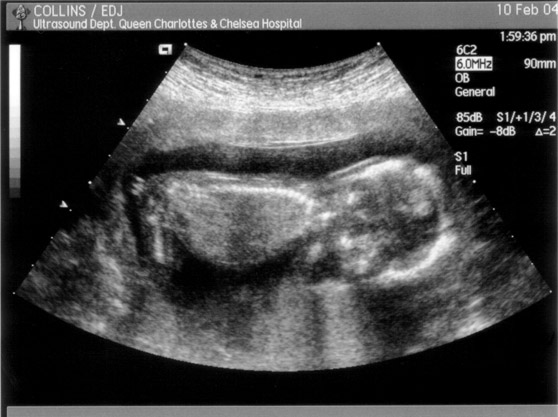

These are the first pictures of our new baby, (due on the 4th August), taken during Tracey's first ultrasound scan on 10th February.

In this one the baby's head is on the right and is looking straight down: